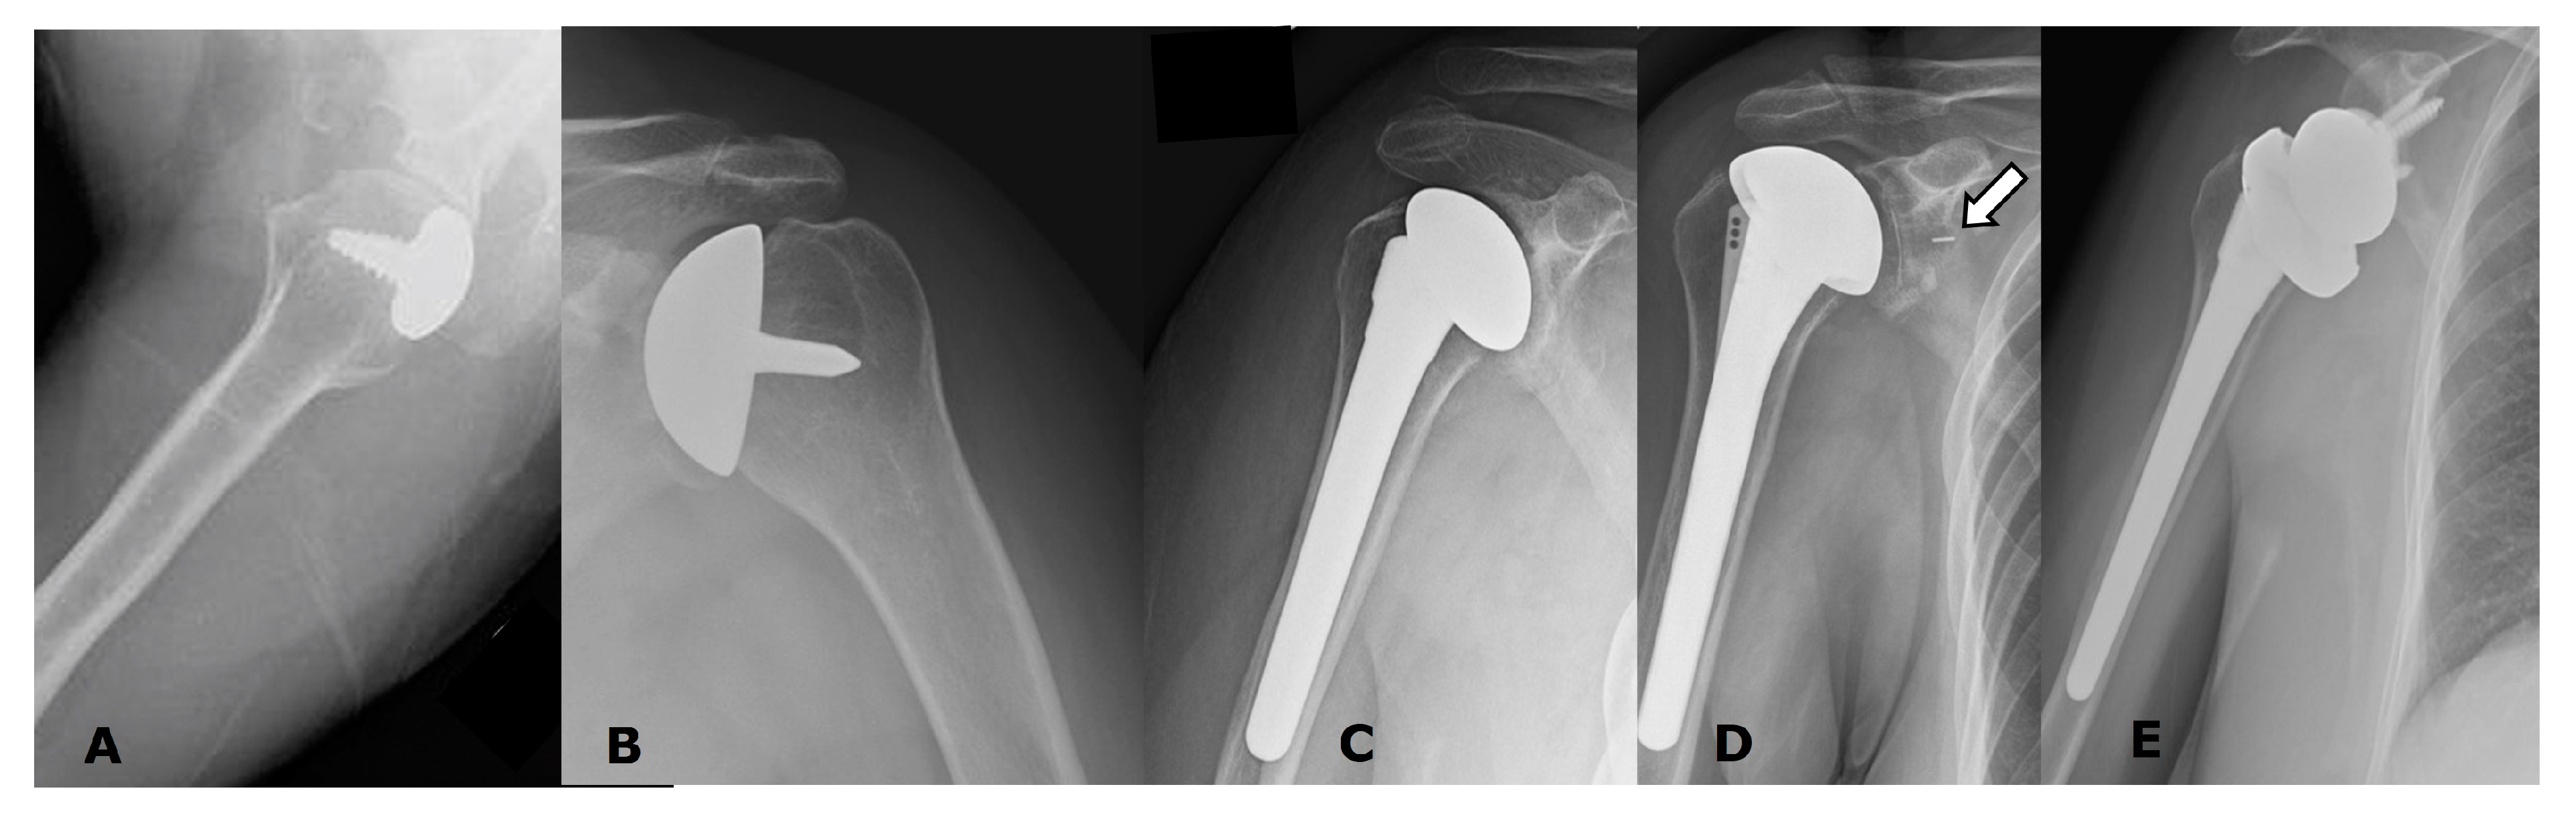

5. Arthroplasty Types

5.1. Anatomic Arthroplasties

5.1.1. Humeral Head Resurfacing/Stemless Hemiarthroplasty (HHRA)

5.1.2. Hemiarthroplasty (HA)

5.1.3. Anatomic Total Shoulder Arthroplasty (ATSA)

5.2. Reverse Arthroplasty

Reverse Total Shoulder Arthroplasty (RTSA)

5.3. Revision Shoulder Arthroplasty